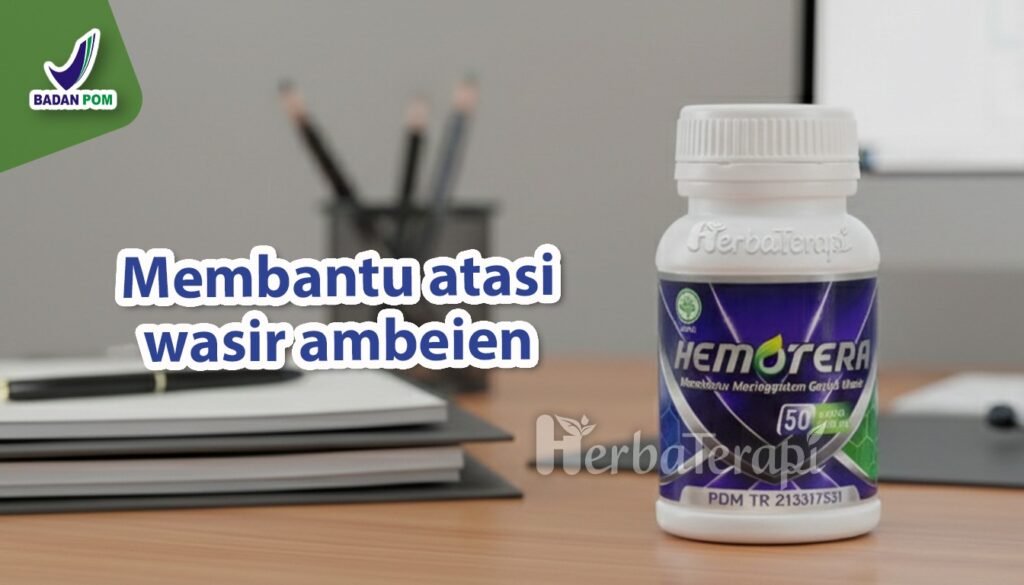

Bagi penderita yang ingin mengatasi keluhan secara alami, Hemotera hadir membawa manfaat dari ekstrak daun ungu. Kombinasi temu putih dan lidah buaya di dalamnya bekerja sangat efektif untuk mendinginkan jaringan yang iritasi.

Kandungan rimpang kunyit serta sambiloto bertindak sebagai antiseptik alami guna mempercepat penyembuhan luka di dinding anus. Hemotera membantu mengurangi pembengkakan serta menghilangkan benjolan ambeien baik dalam skala ringan maupun kondisi berat.

Mewaspadai bahaya tersembunyi seks anal sejak dini akan menyelamatkan fungsi sistem pembuangan dari kerusakan yang menyiksa. Produk ini sudah terjamin aman karena memiliki sertifikasi resmi dari BPOM dan label Halal Indonesia.

Segera dapatkan Hemotera untuk mengempiskan benjolan ambeien agar duduk kembali nyaman tanpa rasa perih menusuk.